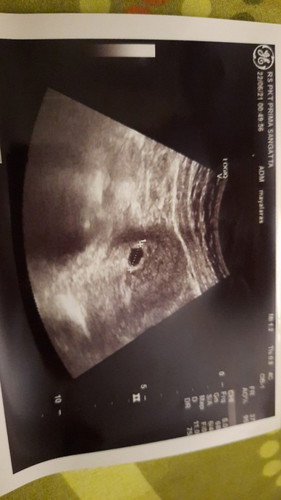

Assalamualaikum bunda semua, hari ini saya kontrol kehamilan, baru 5week, apakah memang msh belum ad isi dlaam kantong tsb? Saya nikah sudah 4 tahun jalan 5,ini kehamilan kedua,yg pertama april kmren usia 8week kuretase karena kehamilan BO. Trimakasih yaa jika ad yg berkenan sharing 😊#firstbaby #ingintahu

Baca lagiUSG usap perut atau transvaginal? klo pakai USG tranvaginal biasanya di usia 6 week udh bisa keliatan bakal janin. dan d usia 7 week detak jantung udh bisa kedengeran. klo USG usap perut biasanya baru terdeteksi di usia 10 ke atas. klo emang mau lebih akurat minta USG tranvaginal Bun.. karna alat nya bener2 ngecek dri dalem Deket mulut rahim.

maksimal 10week harus sudah ada janin,y... kalau 5w mungkin baru penebalan n terdapat kantung yg trlihat. relaks n jgn stress.. positif thinking aja... 3 minggu kedepan coba kembali ke dokter buat usg lagi. semangat bunda.

Waktu saya aja 6 minggu masih kantung Bun, nnti kehamilan 2 bulan 1 Minggu kontrol lagi dan USG ada perkembangan gak janinnya

kemarin minggu ke 5 terlihat kantong ajja tp minggu ke 6 sdh kelihatan bun